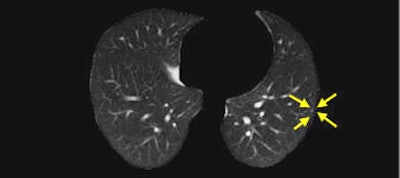

| Nodules detected by ROI detection system. Top, small nodule with inconspicuous intensity difference with surrounding lung context. Below, small well-formed nodule. Third from top, small nodule hardly distinguishable from the background and nearby thin vessels. Bottom, small irregularly shaped nodule. All images courtesy of Javad Alirezaie, Ph.D. |